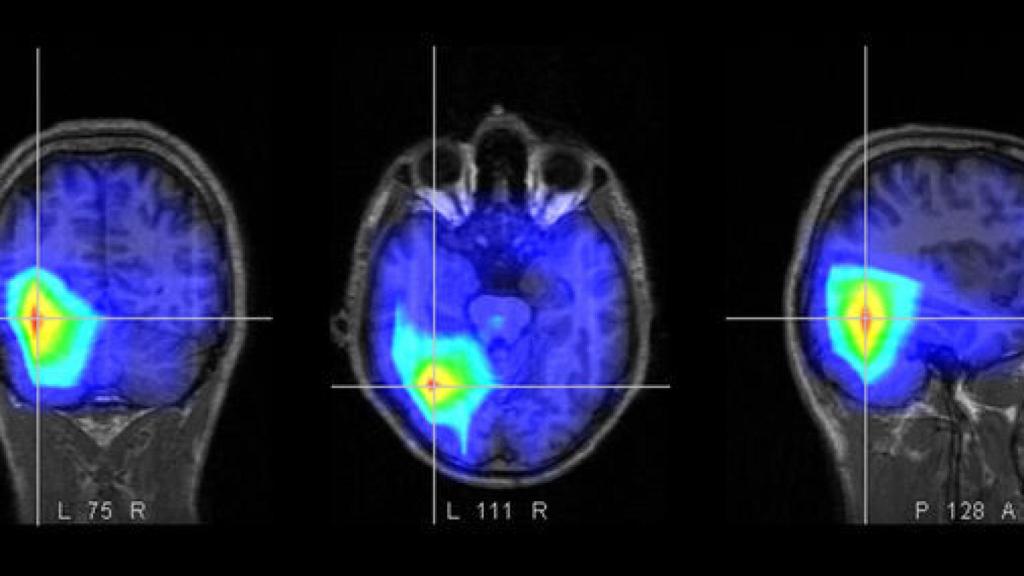

Por lo que comenta en su estudio, tras analizar imágenes de resonancia magnética de 550 hombres y mujeres sanos de diversos hospitales de Londres, la temporada del año en que nacemos se puede identificar según la morfología de nuestro cerebro. Pantazatos dividió las temporadas de la siguiente manera: Invierno (del 23 de diciembre al 19 de marzo), Primavera (del 22 de marzo al 19 de junio), Verano (del 22 de junio al 21 de septiembre) y otoño (del 24 de septiembre al 20 de diciembre).

En el caso de los hombres, aquellos que habían nacido en otoño o invierno tenían más materia gris en el surco temporal superior izquierdo (STG) que los nacidos en primavera o verano. Los que habían nacido a finales de diciembre eran los que tenían más materia gris tenían en esta zona, y los nacidos a finales de junio los que menos.

Finalmente, Pantazatos comprobó si es posible adivinar en que estación del año nació una persona con tan solo observar su cerebro. Lo curioso es que descubrió que si era posible adivinarlo en mujeres, por su cantidad de materia gris, pero no en hombres. Midió la cantidad de materia cerebral en la corteza del lóbulo frontal, lóbulo parietal y el cerebelo, y fue capaz de clasificar la temporada de nacimiento de las mujeres con una precisión del 35% (no es muy preciso, pero algo es algo). Una de los obstáculos del estudio es que no había datos sobre la procedencia de nacimiento de los participantes, un dato importante por la existencia de los dos hemisferios terrestres.